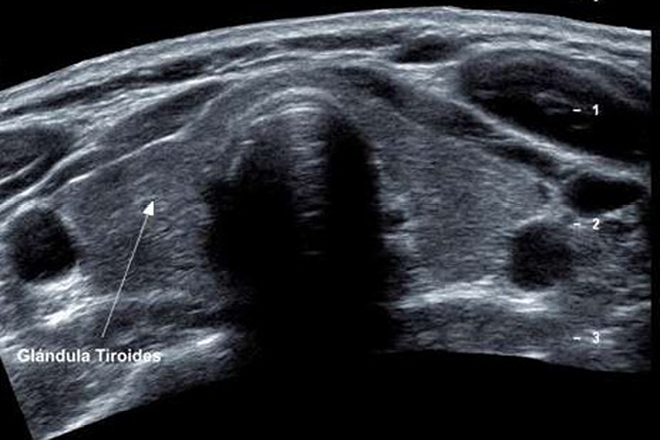

El estudio detallado de las imágenes ecográficas de estas patologías es esencial, requiriendo un entrenamiento visual para dominar esta técnica. Con este fin, se llevó a cabo un proyecto de investigación para realizar diagnósticos clínicos ecográficos de los nódulos y masas tumorales de la Tiroides.

Los hallazgos ecográficos permitieron clasificar las patologías, destacándose el bocio nodular con diferentes patrones de imagen como tiroides aumentado de tamaño con ecogenicidad irregular y tiroides agrandado con baja ecogenicidad.

Al comparar los hallazgos con estudios citológicos, se identificaron casos de bocio nodular, adenomas, tiroides malignos, quistes tiroideos y tiroiditis.

El Ultrasonido Diagnóstico de Tiroides es útil para evaluar diversas alteraciones relacionadas con esta glándula, como nódulos, adenomas, hiperplasias, restos quirúrgicos, neoplasias, metástasis y en pacientes con antecedentes de radioterapia en el cuello, siendo también una herramienta para guiar procedimientos como la biopsia con aguja fina y el tratamiento con etanol.